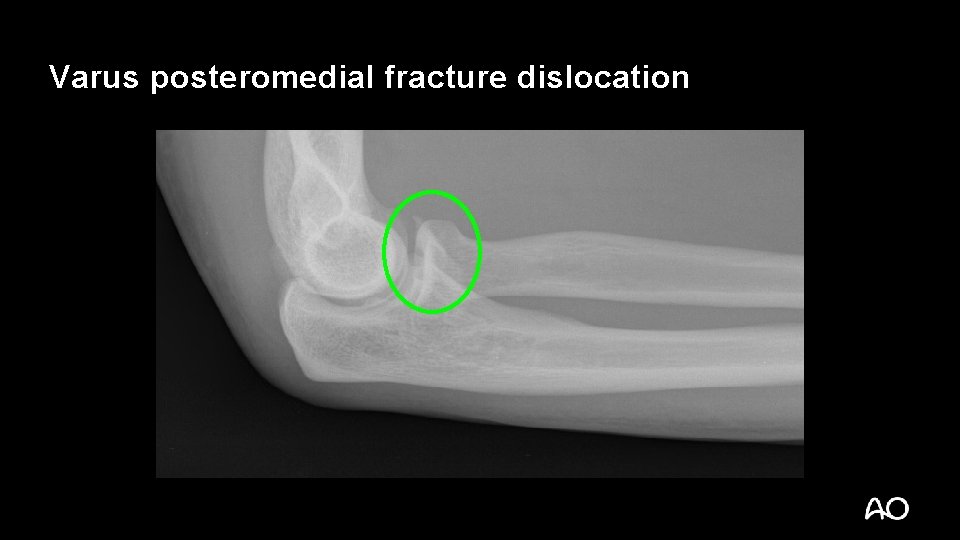

Varus posteromedial fracture dislocation • Recently described injury pattern • Failure to recognize can result in poor outcomes (arthrosis) • Easy to overlook (occasionally small coronoid fractures)

Varus posteromedial fracture dislocation Courtesy of David Ring • Stress views demonstrate that the LCL is ruptured and the elbow is unstable • Results can be poor without operative treatment

Varus posteromedial fracture dislocation